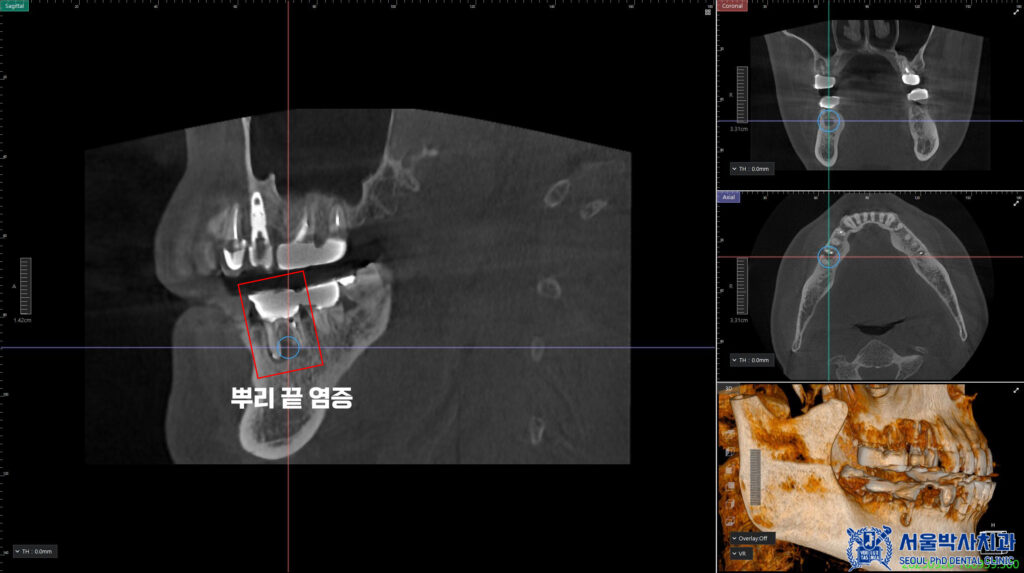

그 다음 치료는 오른쪽 아래로,

CT상에서도 보이는

뿌리 끝 염증과 충치로 인해

골소실이 진행될만큼

썩어있는 상태였습니다.

그래서 해당 치아는 발치를

진행하기로 하였습니다.